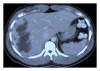

Bile leaks from the intrahepatic biliary tree are an important cause of morbidity following hepatic surgery and trauma. Despite reduction in mortality for hepatic surgery in the last 2 decades, bile leaks rates have not changed significantly. In addition to posted operative bile leaks, leaks may occur following drainage of liver abscess and tumor ablation. Most bile leaks from the intrahepatic biliary tree are transient and managed conservatively by drainage alone or endoscopic biliary decompression. Selected cases may require reoperation and enteric drainage or liver resection for management.